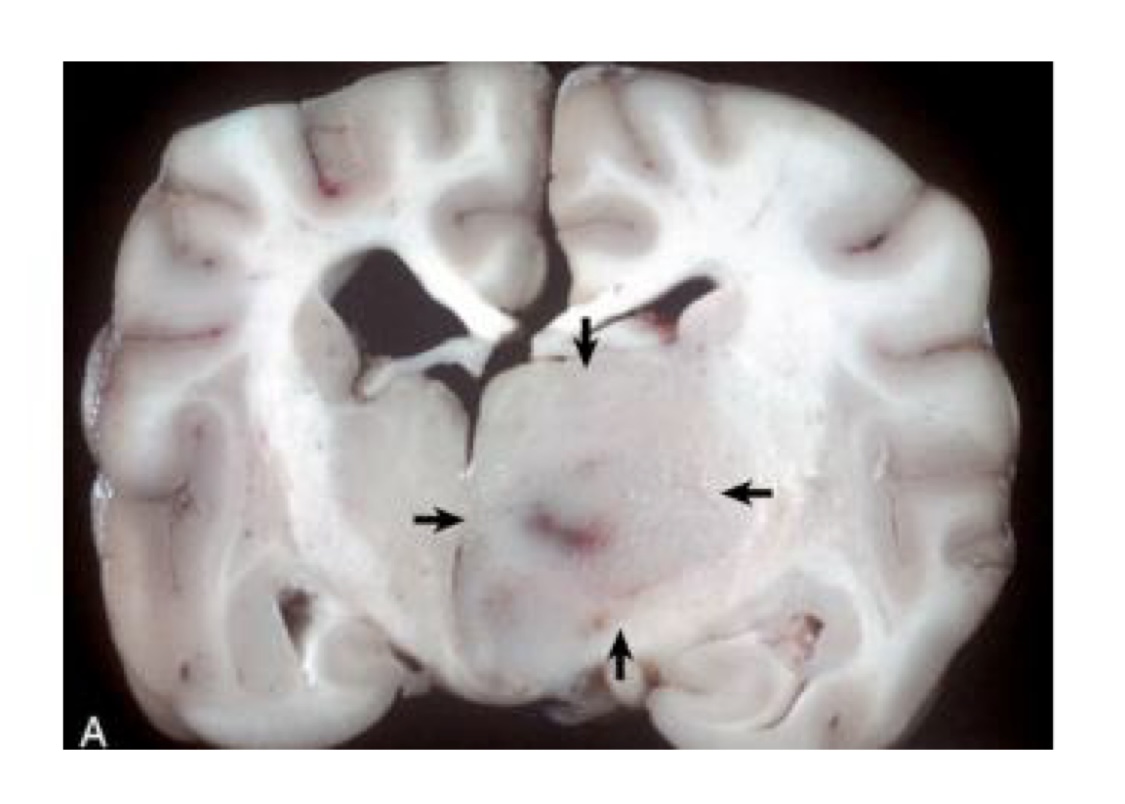

what is this?

astrocytoma

right hemisphere contains a poorly demarcated, nonencapsulated, expansile mass

lesion has displaced the midline to the left and compressed the right lateral ventricle